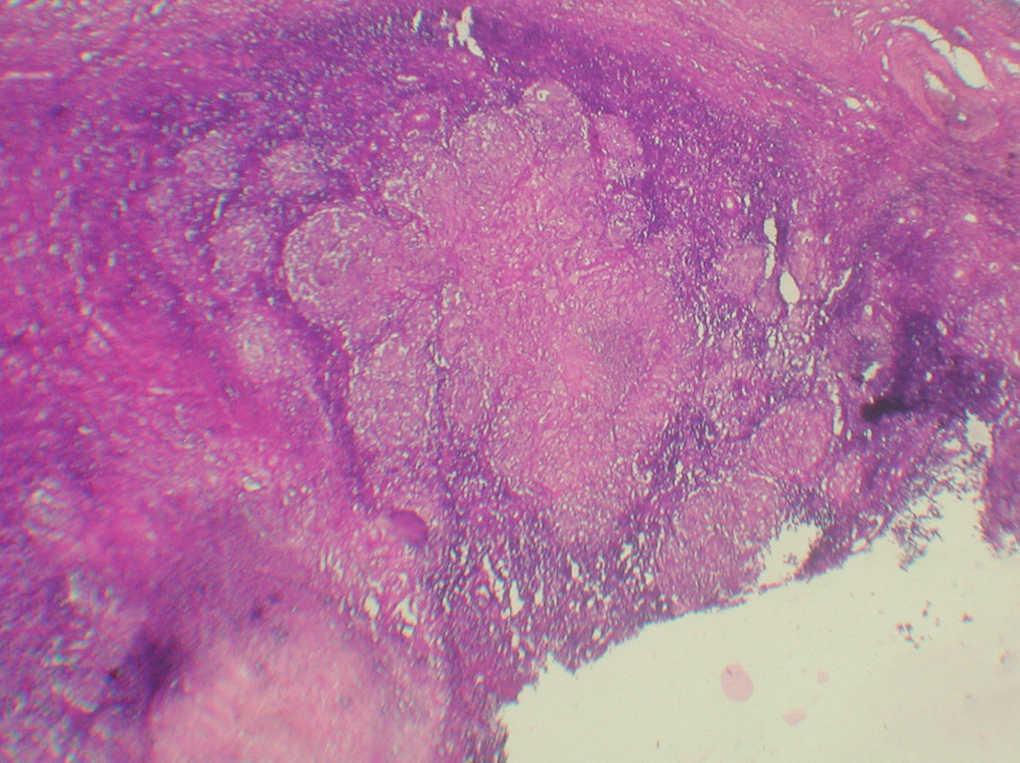

En la analítica general se apreciaba una anemia mixta ferropénica y de trastorno crónico, hipoalbuminemia y aumento de a2 y gammaglobulinas a expensas de IgM e IgG. Las serologías para el virus de la inmunodeficiencia humana (VIH) y lúes fueron negativas y en la serología hepática se detectó una hepatitis A pasada. Se realizaron cultivos del exudado cicatricial para aerobios, anaerobios y micobacterias y tan sólo se evidenció una contaminación por Staphylococcus epidermidis. La baciloscopia del exudado también fue negativa. Se practicó un Mantoux que fue fuertemente positivo, y se formó una placa 25 mm de diámetro a las 48 h y de 30 mm a las 72 h. La radiografía de tórax era normal y las de columna y miembros inferiores mostraron un acortamiento de la pierna izquierda con escoliosis compensatoria. La resonancia magnética de miembros inferiores mostraba una masa de 4 cm próxima al paquete vascular inguinal, de aspecto heterogéneo en cuyo interior se apreciaban zonas hipodensas, sugerentes de necrosis y que mostraba un crecimiento hacia el paquete vascular ilíaco, asociando fascitis en el músculo obturador externo. Se practicó una punción-aspiración con aguja tina (PAAF) del ganglio inguinal cuyo resultado fue una linfadenitis granulomatosa, con tinciones de Ziehl-Nielsen, Gomori y Giemsa negativas. Finalmente se realizó una extirpación de una adenopatía inguinal superficial y dolorosa cuyo estudio anatomopatológico (fig. 3) fue similar al de la PAAF, con tinciones para parásitos, hongos y micobacterias negativas. La baciloscopia también fue negativa pero el cultivo para micobacterias en medio BACTEC MGTI fue positivo a los 16 días. Dada la procedencia de la paciente y el desconocimiento de la sensibilidad antibiótica del bacilo se inició el tratamiento con cuádruple terapia: isoniazida, rifampicina, pirazinamida y etambutol ajustados al peso de la paciente, durante 2 meses, seguidos de isoniazida y rifampicina 7 meses más. Además, se asoció un complejo vitamínico B1, B6 y B12 para prevenir la neuropatía periférica asociada a isoniazida. Posteriormente se identificó como Mycobacterium tuberculosis sensible a todos los antibióticos utilizados en primera línea. Se realizaron controles analíticos mensuales para valorar la función hepática que se mantuvo durante todo el tratamiento dentro de los límites normales. La supuración y el dolor asociado se resolvieron en los primeros 20 días. Como único incidente destacado se produjo un embarazo y dados los posibles efectos teratogénicos de la medicación (grupo C) la paciente prefirió que se le practicara un aborto terapéutico.

Fig. 3.--Granulomas tuberculoides confluentes, con degeneración central y corona inflamatoria periférica. (Giemsa, x40.)